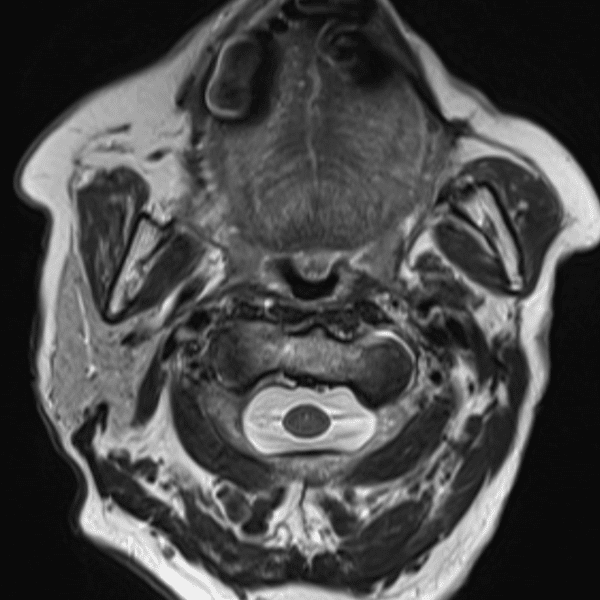

Neck T2WI

3.0T Siemens MAGNETOM Skyra

2D TSE

(L) 0.5×0.7×3.0 mm

(R) 0.4×0.6×3.0 mm

Conventional SwiftMR™ 02:50 01:17 (55% Faster)